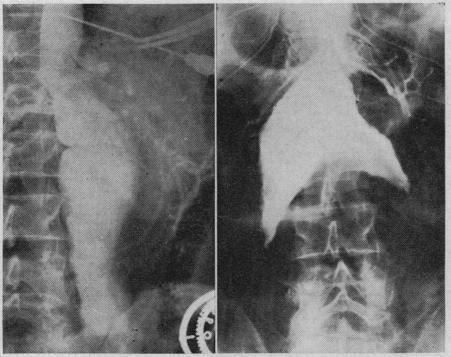

With the use of anticoagulants to prevent recurrence of thrombosis it is now possible to open a major artery which has been occluded by a thrombus, remove the thickened lining with the clot and restore the continuity of the vessel. Free vein grafts have been used successfully to replace arterial segments in the extremities. Vein inlay grafts are preferred in dealing with aneurysms of the abdominal aorta. The aneurysmal wall can be used to support the venous segments. It has been possible to by-pass aneurysms of the abdominal aorta by anastomosing the splenic artery to the left iliac artery. The use of the left superficial femoral artery as a by-pass to supply blood to the right leg is described.

使用抗凝剂预防血栓形成复发后,现在有可能开通一条被血栓阻塞的主要动脉,清除带有血栓的增厚内膜并恢复血管的连续性。游离静脉移植物已成功用于替代四肢的动脉段。在处理腹主动脉瘤时,静脉镶嵌移植物更受青睐。动脉瘤壁可用于支撑静脉段。通过将脾动脉与左髂动脉吻合,有可能绕过腹主动脉瘤。文中描述了使用左股浅动脉作为旁路为右腿供血的情况。